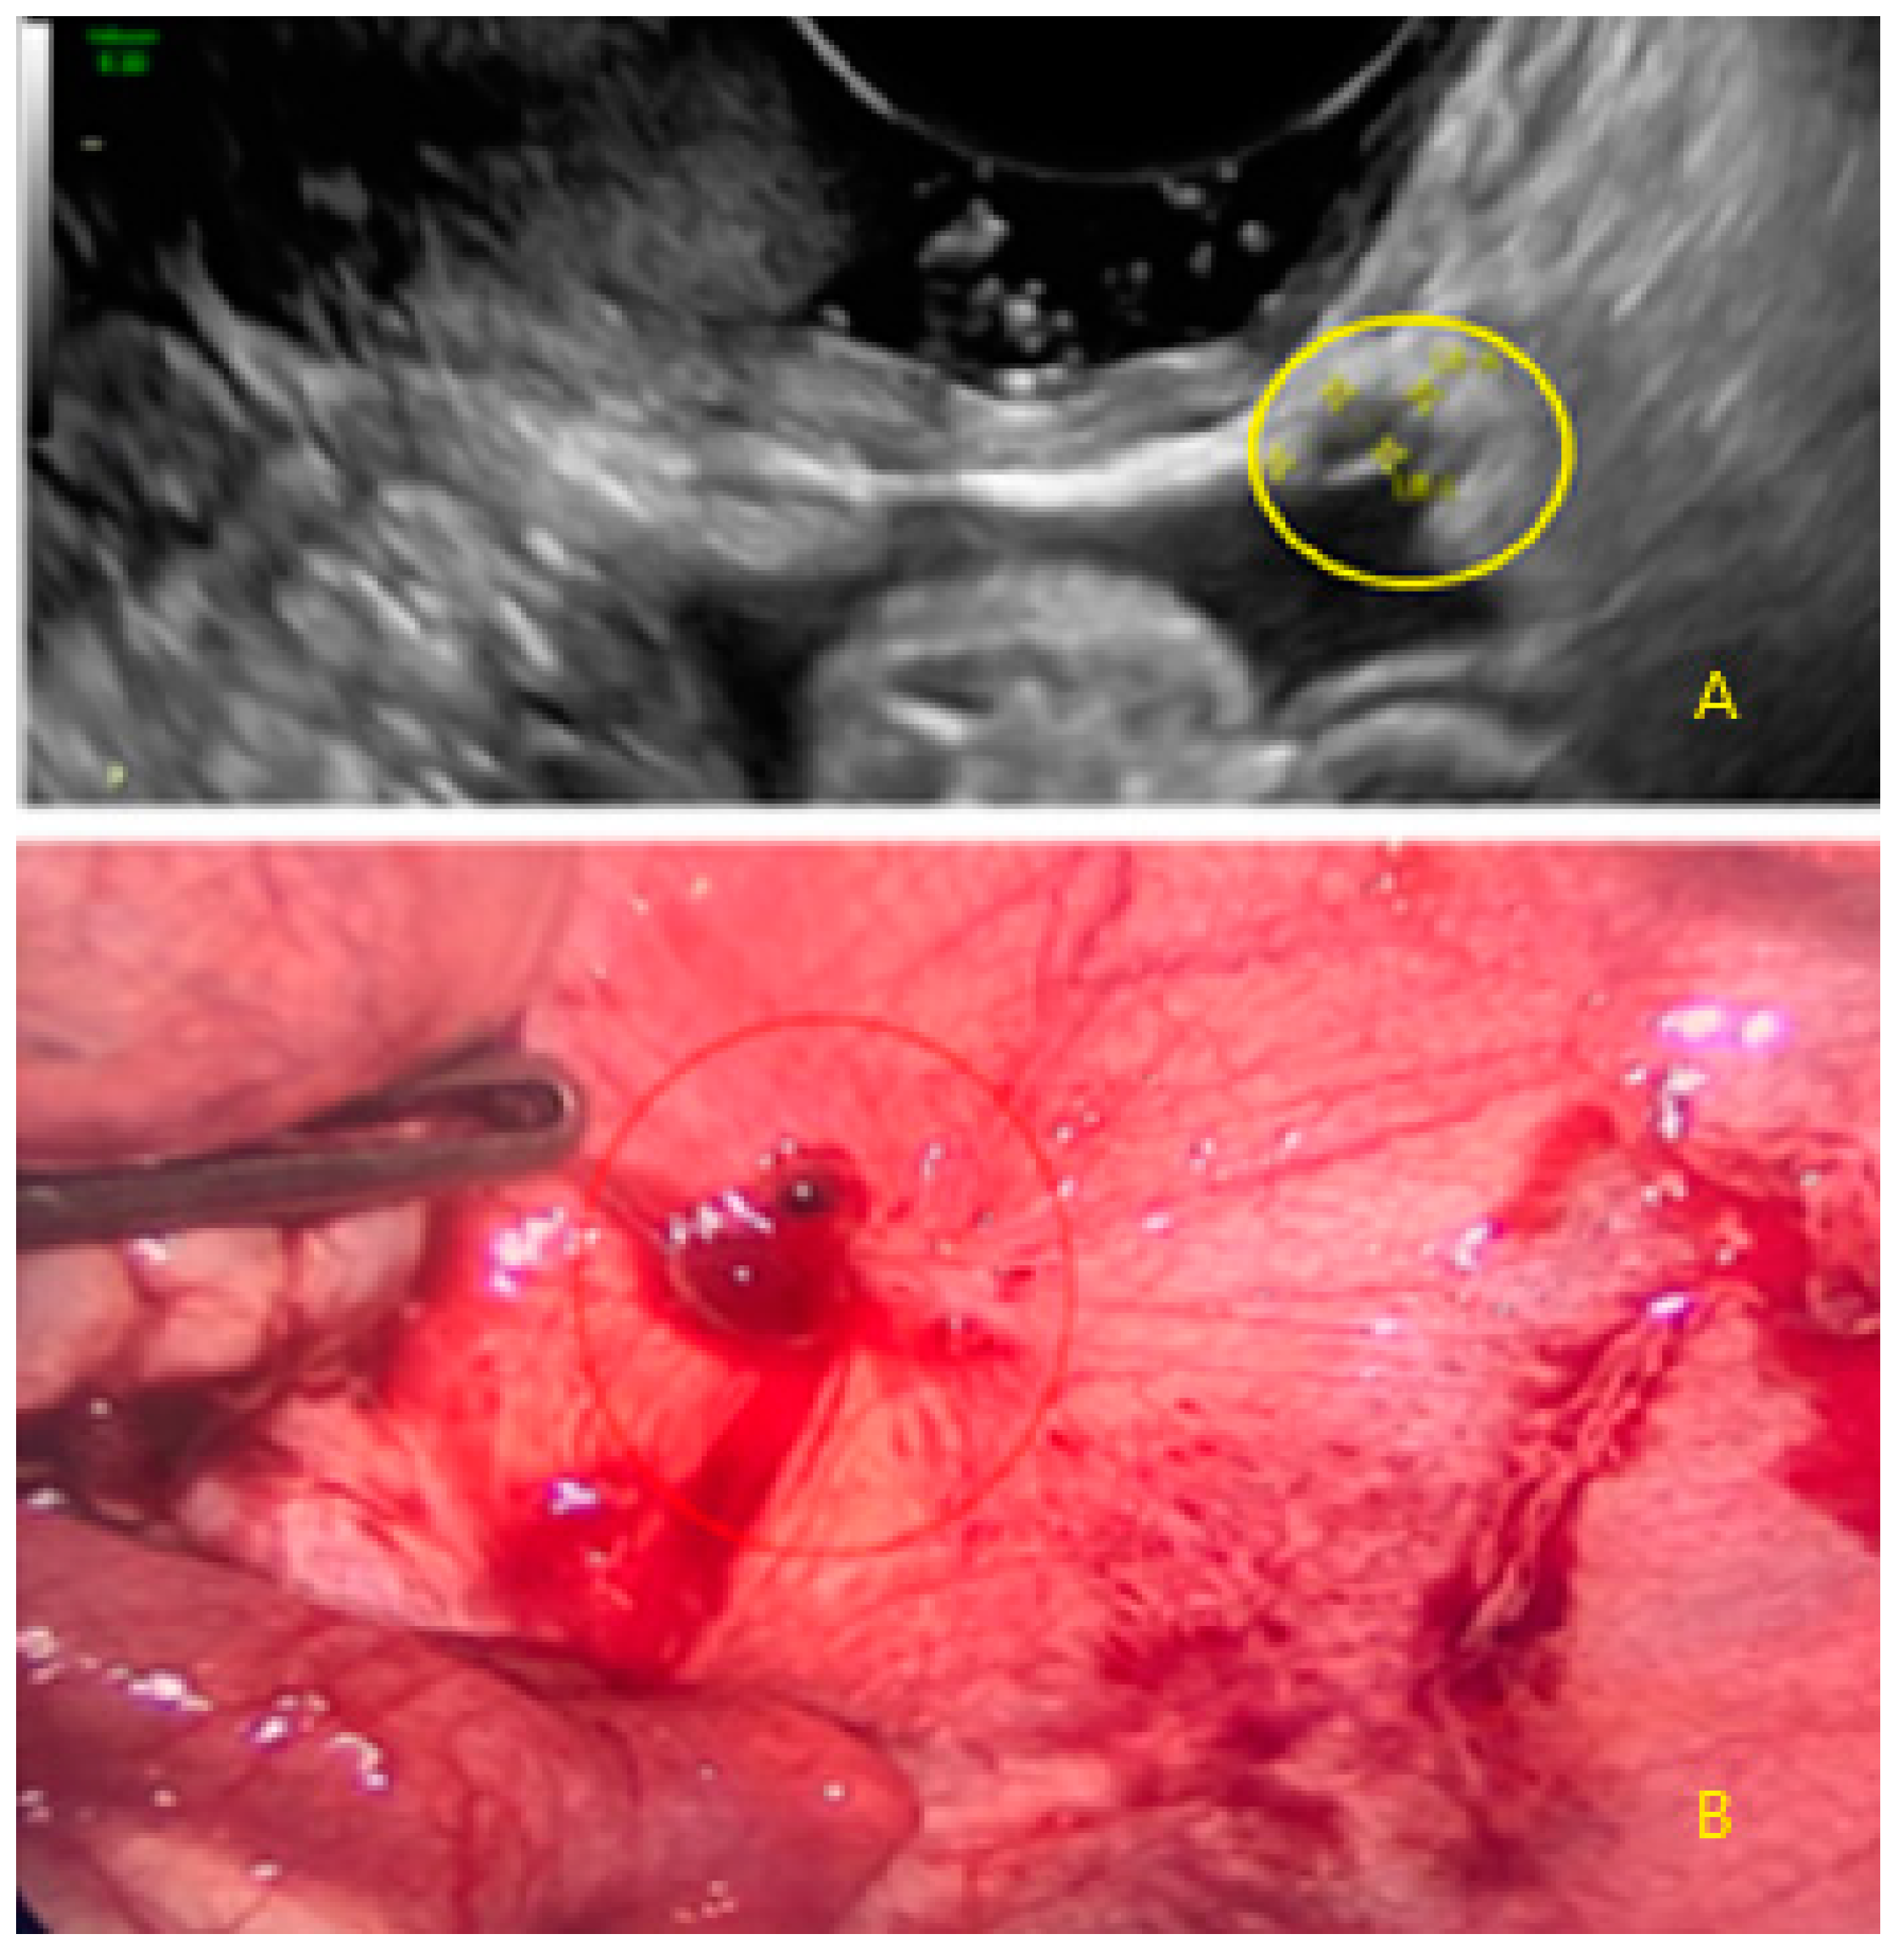

3.3. Cystic Lesions Arranged in a Cluster

4. Discussion